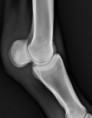

Equipartners blijft niet stil staan en wilt steeds het beste op de markt hebben dus hebben we geïnvesteerd in een gloednieuw direct digitaal systeem. Hier hebben we na het afdrukken direct het beeld op onze beeldscherm. De tijd om 20 foto's te nemen van een paard is even lang als de tijd die we vroeger nodig hadden om één foto te ontwikkelen en te drogen toen we nog met handontwikkeling werkten.

Met dit systeem hebben we haarscherpe foto's, zijn ze gemakkelijk op te slaan én kunnen we met een druk op de knop het volledige dossier naar de eigenaar doorsturen.